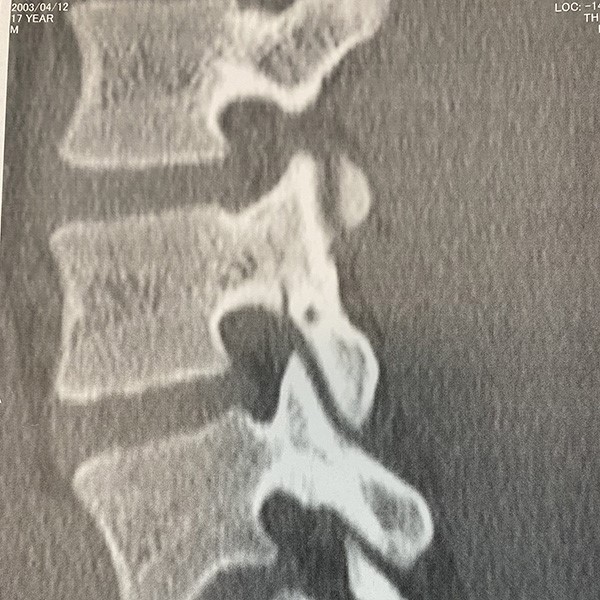

ケガ当初のCT画像